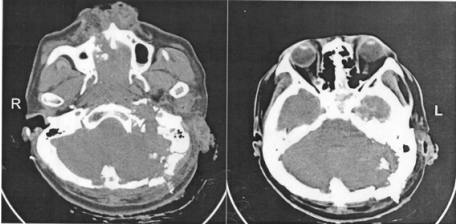

28 之後立即作了頭腦電腦斷層掃描如附圖, 顯示有顱基底骨骨折,依病史及電腦斷層 掃描,貫穿的子彈進入區是在何處?

(A)右鼻骨區 (B)左鼻骨區 (C)左後枕骨區 (D)右後枕骨區

29 警察先生的另一張電腦斷層掃描如附圖, 除了骨折,還有:

(A)左小腦內出血 (B)右小腦內出血 (C)左後腦窩硬腦膜上腔出血 (D)右後腦窩硬腦膜下腔出血